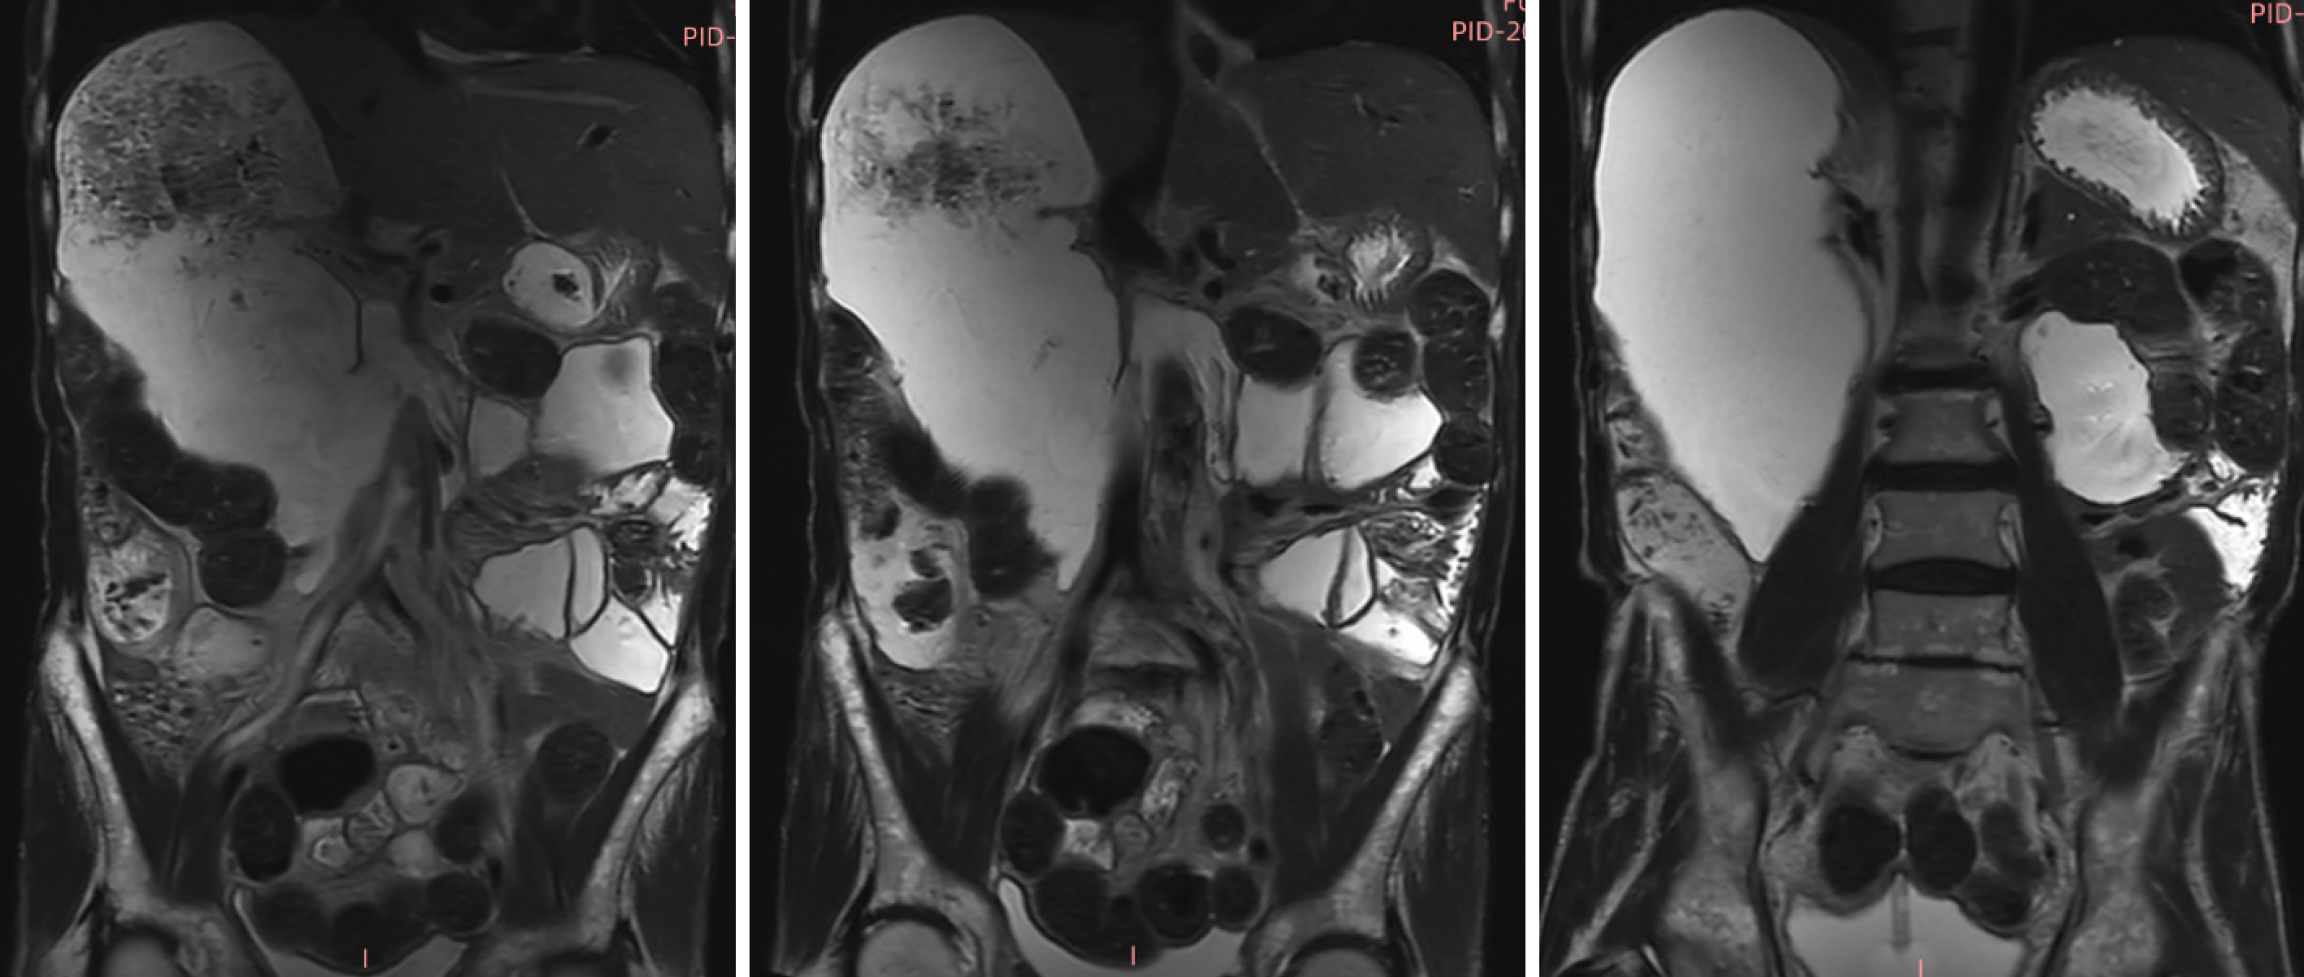

Renal ultrasonography revealed dilation of the left renal collecting system with mild upper ureteral dilatation. Abdominal radiography (Figure 1A) showed right hemidiaphragm elevation and dilated bowel loops with air-fluid levels. The findings of the upper gastrointestinal barium study (Figure 1B) demonstrated mild esophageal dilation, as well as marked duodenal bulb and descending segment dilation with contrast retention. Abdominal CT (Figure 2) revealed duodenal sac-like dilatation with positional changes, narrowing of the horizontal segment, segmental jejunal dilatation, reduced bladder tone, and an indwelling urinary catheter. Abdominal magnetic resonance imaging (Figure 3) revealed significant duodenal and multiple small intestinal dilatations. Gastroscopy revealed reflux esophagitis (LA-B), gastric retention and deformation, and duodenal dilatation with villous atrophy. Colonoscopy revealed a polyp located in the descending colon, which showed an unremarkable anastomotic site.